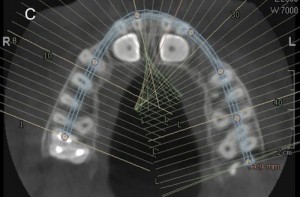

Authors: Andrea Fama , Davide Cavagnetto, Andrea Abate, Andrea De Filippis, Eleonora Mainardi, Luca Esposito

The term dilacerated refers to a dental element that has an alteration of the axial inclination of the crown with respect to the root. Dilaceration can occur at the crown-root junction with...